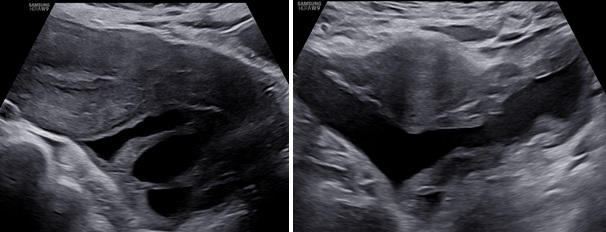

– Siêu âm: Tử cung và 2 buồng trứng bình thường. Ở cùng đồ sau có cấu trúc echo kém không đồng nhất dạng hình ống, có vách ngăn dày thông nhau, kích thước # 84x 89x 37 mm, bờ trong thành u không trơn láng, bên trong có nhiều mảng echo kém dạng mô đặc, tăng sinh mạch máu mức độ 2. Bụng và cùng đồ: không dịch.

– Chẩn đoán siêu âm: Huyết tụ thành nang. Chẩn đoán khác: áp xe phần phụ.

Hình 3: Siêu âm ngã bụng thang xám cắt dọc và ngang cho thấy khối u nằm mặt sau tử cung lan qua hai bên hố chậu.

Hình 4: Siêu âm ngã âm đạo thang xám cho thấy khối u hình ống ở cùng đồ sau nhiều vách ngăn dày thông nhau.